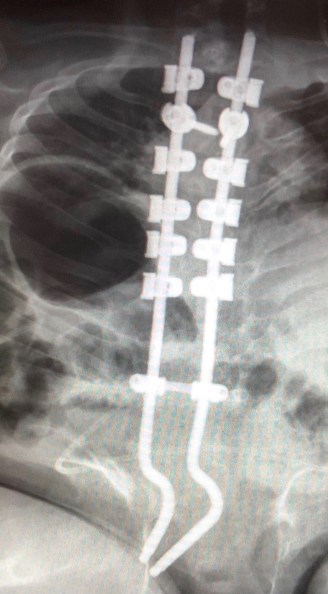

On top of this news, there has also been more bad news concerning the hardware in Lilyan’s back. At the base of this large amount of metal in her back, things were anchored to the piece of sacrum that Lilyan was born with (she is missing most of the sacral bones). Sadly, that anchor point fractured through her little sacrum. This loose end is now protruding away from her spine and into the soft tissue in her lower back, putting her at risk for more tissue damage. You can see this in the X-rays below, especially in the profile view.

Full view of Lilyan’s hardware, placed during her 14-hour surgery on March 20.

You can clearly see the pointy end at the base that is pressing on the soft tissue in her lower back

Her spine surgeon will have to do another surgery to open up her lower back and snip off this end, but everyone is trying to determine the best and safest time to do this surgery. In the meantime, because it’s most prominent in a sitting position, Lilyan has to spend almost all of her time on her stomach. This has been another emotional blow for her, adding to her feelings of helplessness and loss of normal life and independence, but the other kids work so hard to find ways to keep her included in daily life and actively engaged mentally and as physically as possible. Our kids are working so hard to help us care for everyone, and we could not survive with out their loving and unselfish service right now.